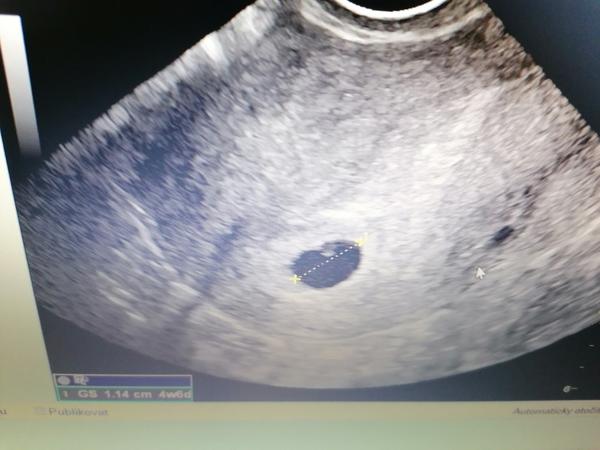

6.tt hematom u miminka. Vsřebal se? Máte zkušenost?

Ahoj jsem v 6tt a chci se zeptat udrželo se vám miminko vstřebal se?

Dostala jsem utrogestan 1-0-1. Nevím jak je velký vím že to dr říkal ale mě úplně vypla hlava.